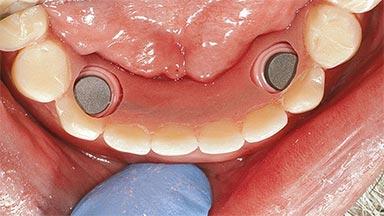

# of Implants 2

Type of Implants One-Piece

Attachment One-Piece

Prosthesis Type RDP

Defining Characteristics Fully edentulous lower jaw to be rehabilitated with an implant-borne removable overdenture

Loading Protocol Conventional/early